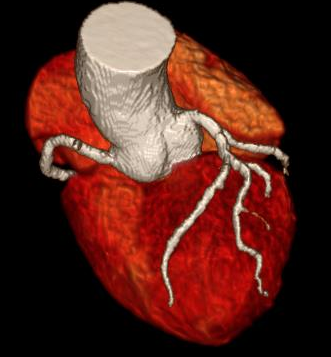

如果把心脏比作人体的“发动机”,那么冠状动脉就是给这个发动机输送燃料的“油管”。一旦这些油管堵塞,心脏就可能“罢工”。今天我们要说的磁共振心脏冠脉检查(简称心脏磁共振),就像给心脏油管做“无创体检”,不用开刀、没有辐射,就能看清心脏血管的健康状况。

三、检查能发现什么危险信号

1. 血管堵没堵:

- 就像检查水管有没有锈迹,能看清血管狭窄程度

- 提前发现血管里的“垃圾”(斑块),特别是那些容易破裂的危险斑块